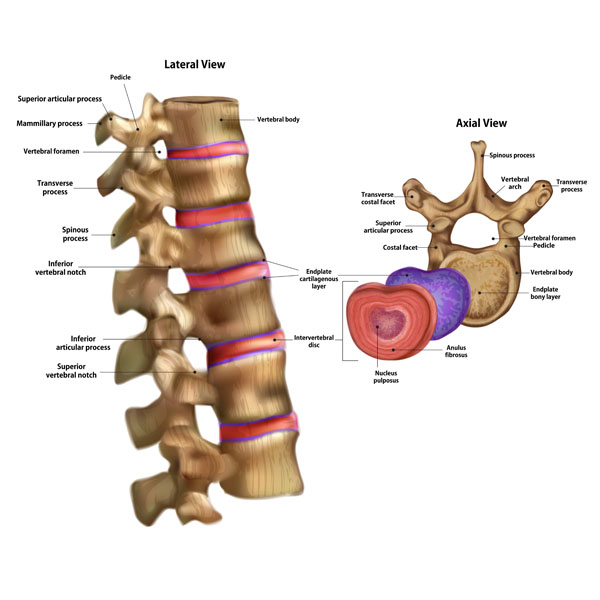

Here we see an illustration with two views of the human vertebral column, emphasizing the anatomy of individual vertebrae. On the left, we have a lateral view of a section of the vertebral column, and on the right, an axial view of a single vertebra.

Starting with the lateral view, we see a sequence of vertebrae aligned. Each vertebra consists of a vertebral body, which is the thick, disc-shaped anterior portion forming the robust, weight-bearing part. The vertebral foramen is a hollow space within each vertebra, and collectively, these form the vertebral canal through which the spinal cord passes. Projecting posteriorly from the vertebral body is a bony arch composed of pedicles and laminae, culminating in the midline with the spinous process, which can be felt through the skin down the back.

We also see the transverse processes, which extend laterally and serve as attachment sites for muscles and ligaments. The superior and inferior articular processes articulate with adjacent vertebrae to facilitate movement while maintaining stability. The notches above (superior vertebral notch) and below (inferior vertebral notch) the pedicles combine to form the intervertebral foramina, through which spinal nerves exit the spinal canal.

The intervertebral discs, which provide cushioning between the vertebrae, are depicted between the vertebral bodies. These discs allow for movement and act as ligaments to hold the vertebrae together. The endplate cartilage on the top and bottom of the vertebral bodies interfaces with the intervertebral discs, playing a role in the distribution of nutrients to the disc tissue.

Turning to the axial view on the right, we have a top-down look at a vertebra. Here, the vertebral body forms the bulk of the structure, with the vertebral foramen at its center providing passage for the spinal cord. The spinous process projects posteriorly, and the transverse processes extend laterally. The superior and inferior articular processes are more clearly visible in this view, showing where they would interlock with the adjacent vertebrae. The annulus fibrosus is the tough outer layer of the intervertebral disc, encircling the softer nucleus pulposus, which provides the disc its ability to absorb shock and maintain flexibility.

This detailed view of the vertebrae highlights the complex anatomy that allows for both stability and mobility in the spinal column, as well as the protection it provides to the spinal cord.